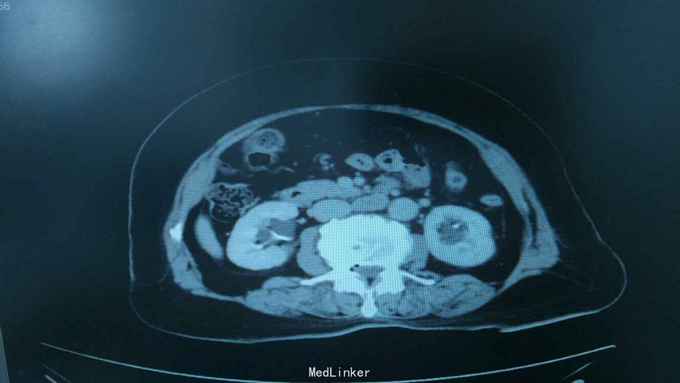

68岁,女性。 主诉:左侧腰痛1年,加重1个月。 病史:1年前无明显诱因出现左侧腰痛,无恶心呕吐,无肉眼血尿。1个月前加重,于外院查泌尿系彩超显示:左肾积液,输尿管显示不清。

诊断:双肾盂旁囊肿 治疗:因患者肾盂未明显受压,疼痛症状不明显,等待观察,暂未予处理。

双侧同时出现的病例并不多见,临床只能通过泌尿系统CTU或增强CT加以鉴别,彩超无法区分肾盂积水及盂旁囊肿。